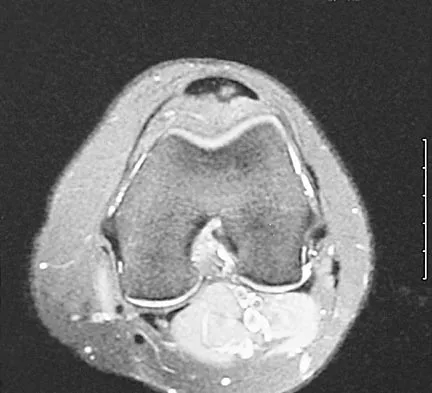

Question 52

Figure 22 shows the MRI scan of a 20-year-old female basketball player who has pain over the anterior knee that interferes with her performance. Examination reveals phase III Blazina patellar tendinosis. Management should consist of

Explanation

Excision of the affected mucoid degenerative area is considered appropriate management in the Blazina classification system. A finding of phase III indicates persistent pain with or without activities, as well as deterioration of performance. With the appearance of the mucoid degeneration and the vigorous activity level of the intercollegiate basketball player, it is unlikely that nonsurgical management will provide adequate relief. When excising the affected degenerative area, care must be taken to retain normal tendon fibers. The defect in the patellar tendon is closed with absorbable sutures, as is the paratenon. Postoperative rehabilitation involves initial mobilization extension, with progressive range-of-motion and mobilization exercises as tolerated and weight bearing as tolerated. Open chain and isokinetic exercises are delayed until full range of motion and mobility is obtained, generally within 4 weeks. A return to activities is achieved by 80% to 90% of athletes, although there may be occasional activity-related aching for 4 to 6 months after surgery. Blazina ME, et al: Jumper's knee. Orthop Clin North Am 1973;4:665. Kelly DW, Carter VS, Jobe FW, Kerlan RK: Patellar and quadriceps tendon ruptures: Jumper's knee. Am J Sports Med 1984;12:375-380. Krums PE, Ryder B: Operative treatment of patella tendon disorders. Operative Techniques Sports Med 1994;2:303.